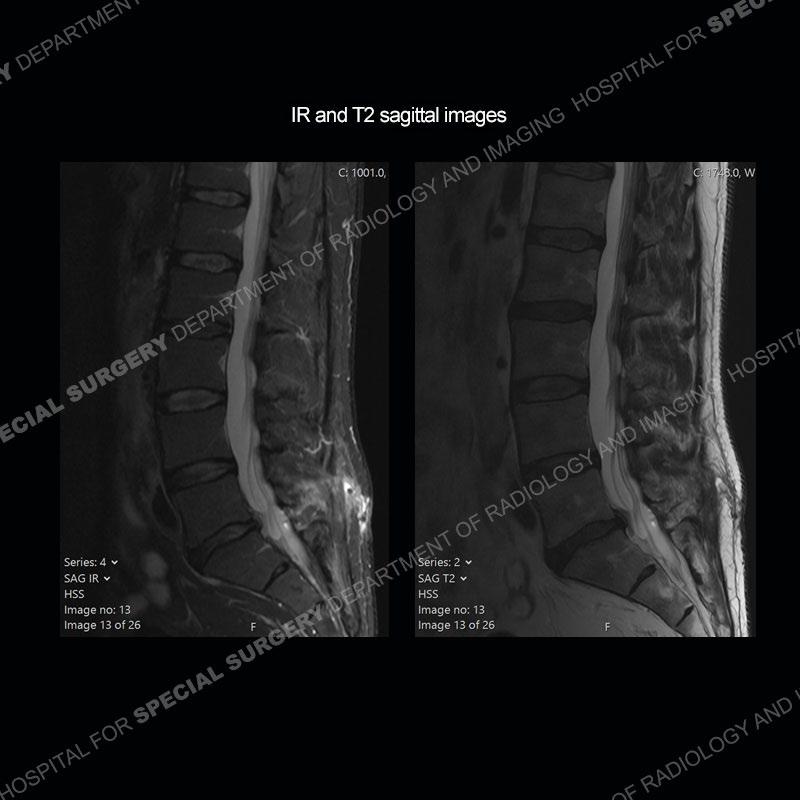

Post operative changes are seen on the left side at L5-S1 where there is near complete removal of the left sided L5 lamina, partial resection of the left L5-S1 facet joint, and resection of the left sided ligamentum flavum. In the anterolateral epidural space about the subarticular recess is a mass that demonstrates similar T1 and T2 signal characteristics to the adjacent degenerated disc. There is enhancement about the periphery of the mass, but the majority of this somewhat geographic or polyploid mass demonstrates no enhancement. The mass exerts prominent mass effect on the left S1 axillary sleeve/proximal nerve root. The left S1 nerve root shows enlargement and increased enhancement as compared to the contralateral right side.

Diagnosis: Recurrent Disc Herniation

Not as much of a diagnostic dilemma as some other cases but more so just a very nice example of what can be a difficult assessment at times. The evaluation of granulation tissue/scar/epidural fibrosis vs. disc herniation particularly in the earlier post operative period can be very difficult. Clues that can assist in identifying a disc herniation are a more geographic or polypoid nature to the mass, signal characteristics similar to the adjacent degenerated disc, mass effect upon the thecal sac/adjacent neural structures, and a typical enhancement pattern. As the disc material is avascular, as long as imaging is performed in a relatively rapid fashion after contrast administration (within 20-30 minutes), the granulation tissue around the disc will enhance but the disc material itself will not. If there is a marked delay between contrast administration and imaging, there may be diffusion of contrast into the disc making the assessment very difficult. The marked utility of contrast to help delineate disc vs. scar has led to our institution employing contrast fairly uniformly within the first two years following surgery.